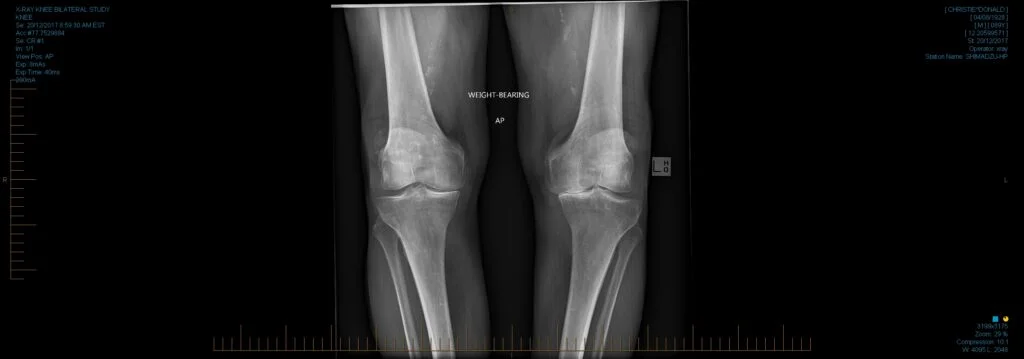

How knee arthritis is diagnosed

- Imaging tests:

- X-rays to assess joint space narrowing and bone changes